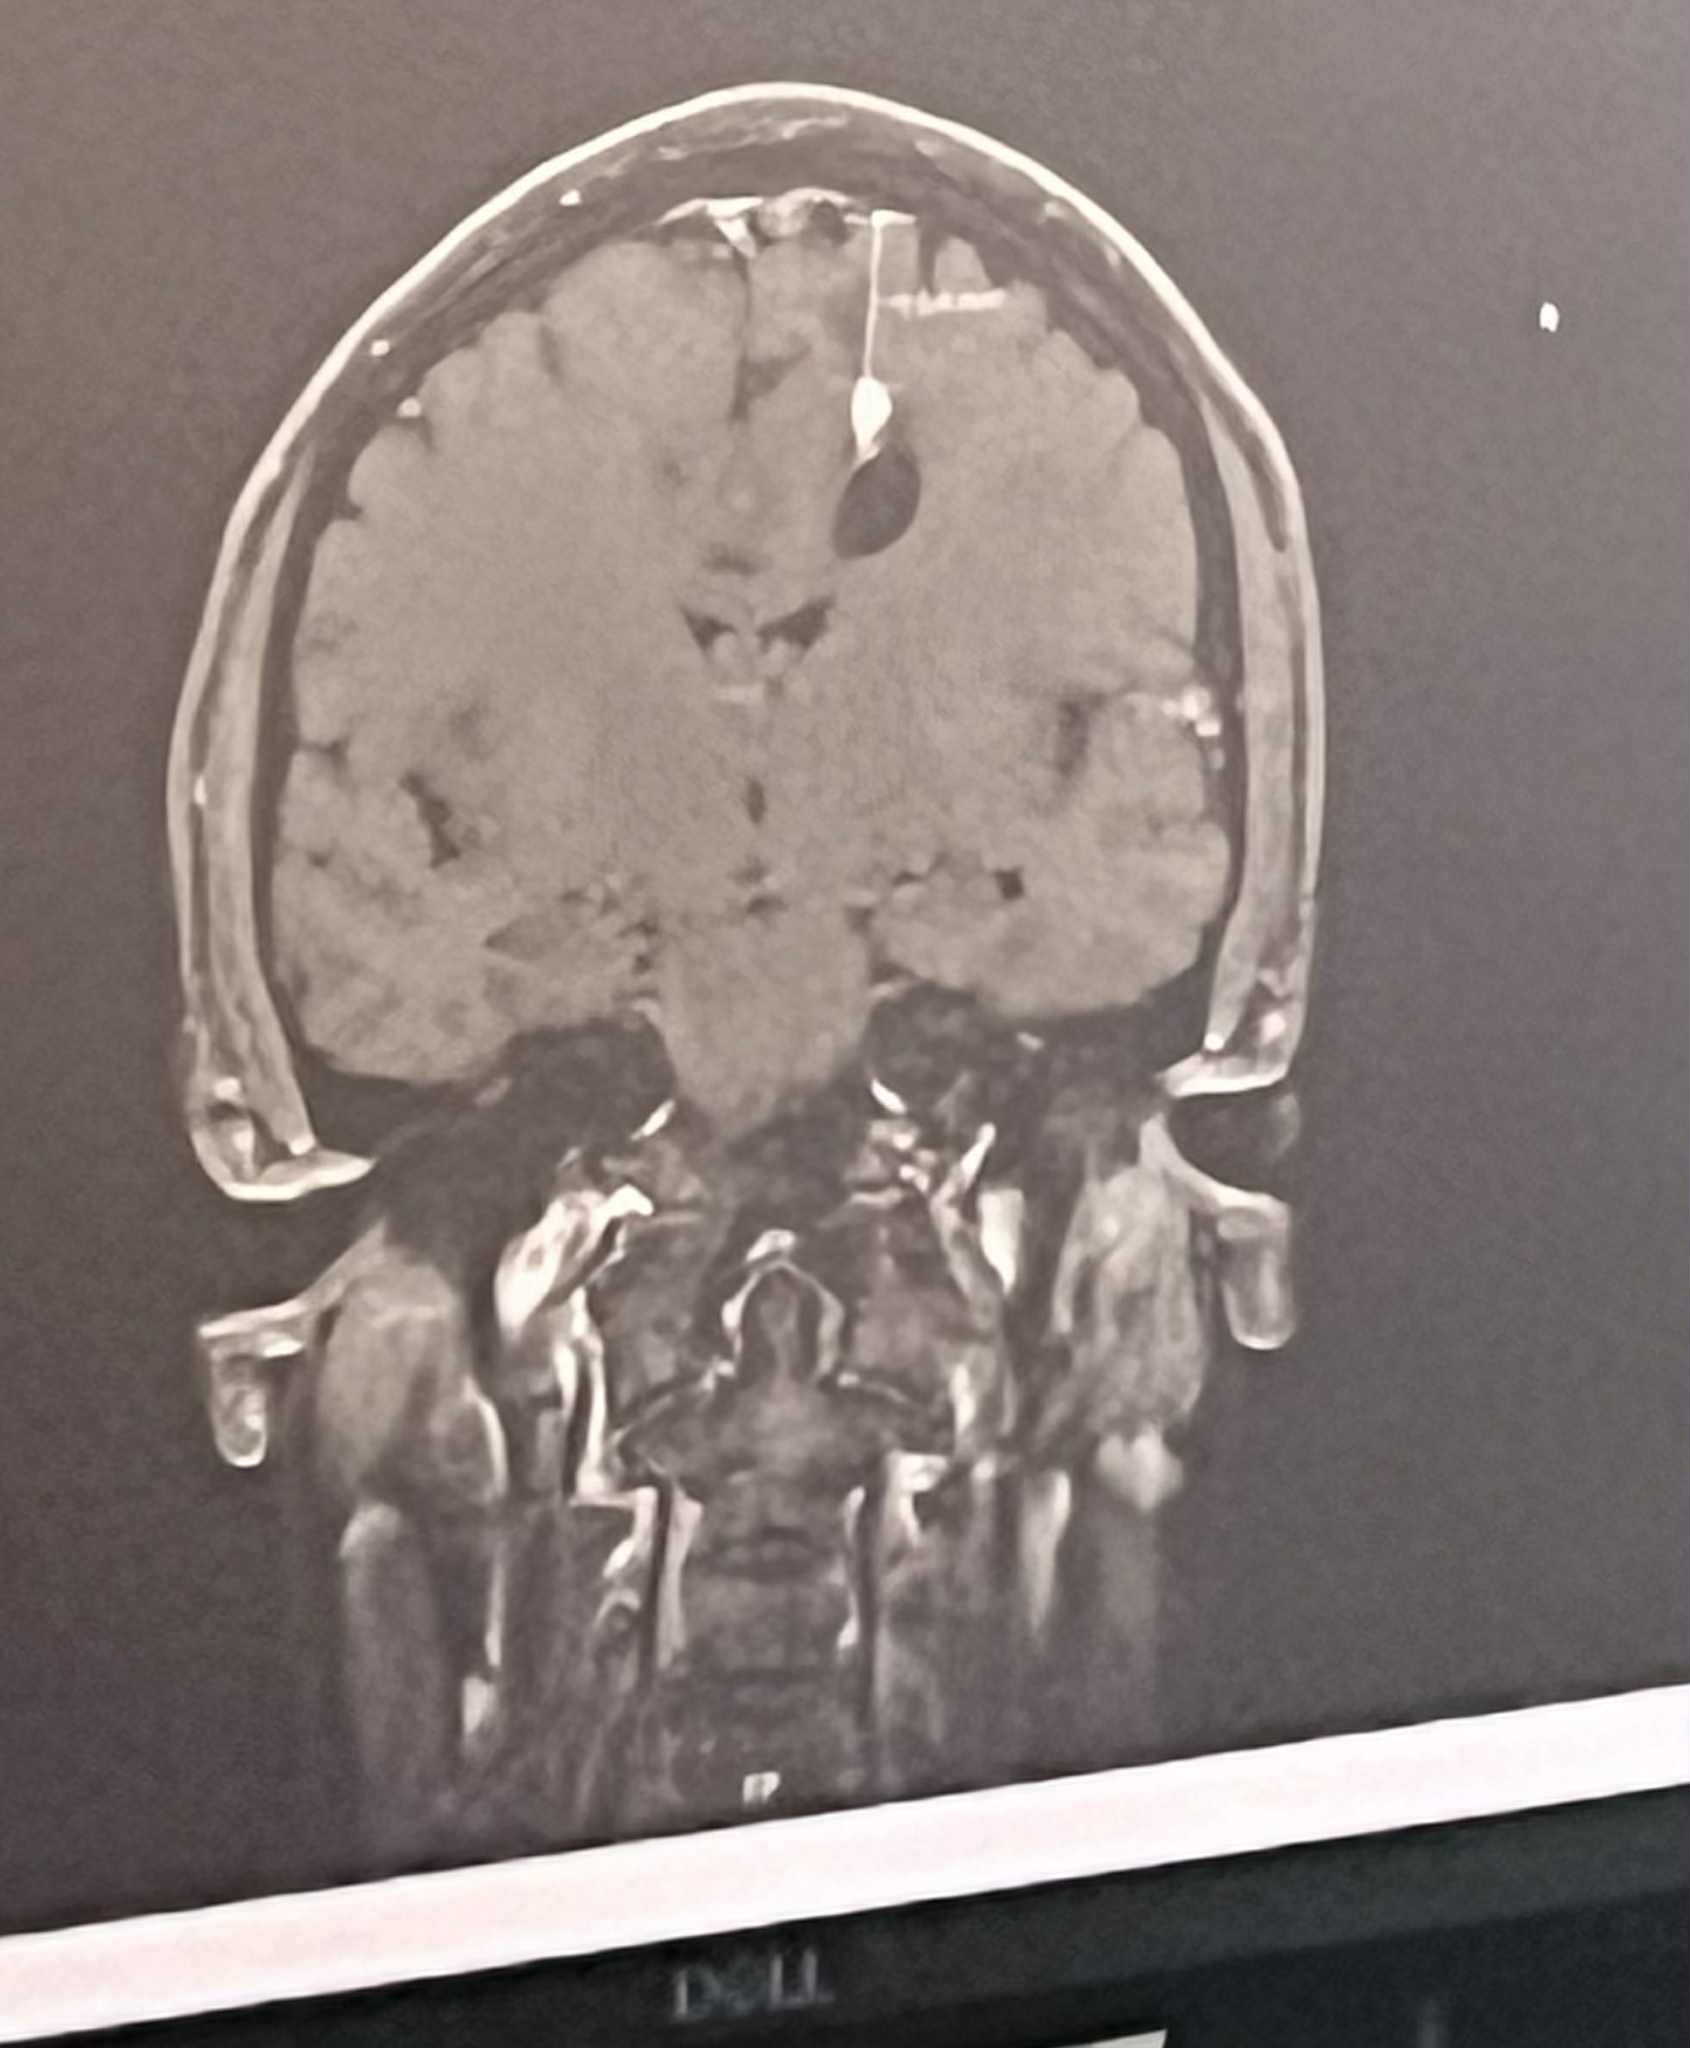

My sister is currently hospitalized with a cancerous brain tumor, a cyst, and significant edema (swelling) in her brain. She’s an inpatient at Springfield CoxHealth, room 845, about 1.5 hours from home, and will remain there through at least Saturday morning while doctors run full-body scans to check for additional tumors and perform a functional MRI to determine if and how her tumor can be safely removed.

In addition to symptoms caused by the tumor, she is now considered at risk for seizures. She’s being treated with steroids to reduce brain swelling, insulin, and continues thyroid care. Her medical team has also placed her on a strict diet requiring 180g of protein daily to support her body during this time.